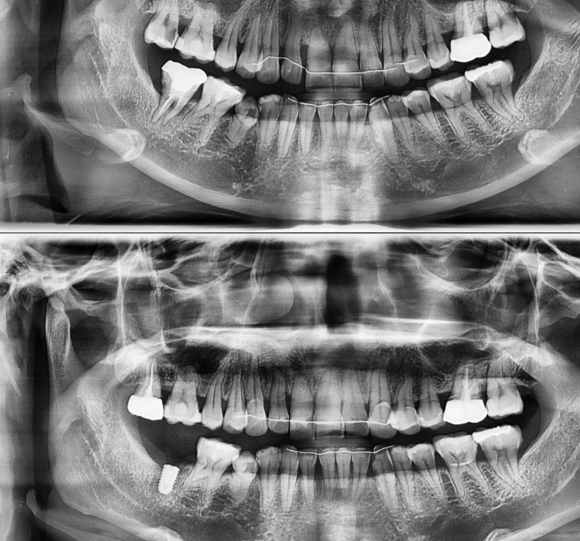

2022.4.20 발치 후 즉시식립

저희 숭실대 입구역 리더스진 치과는 한달 평균 임플란트 60~100개를 꼼수 없이 가장 좋은 재료와 기술로 원칙적으로 식립하는 치과입니다.